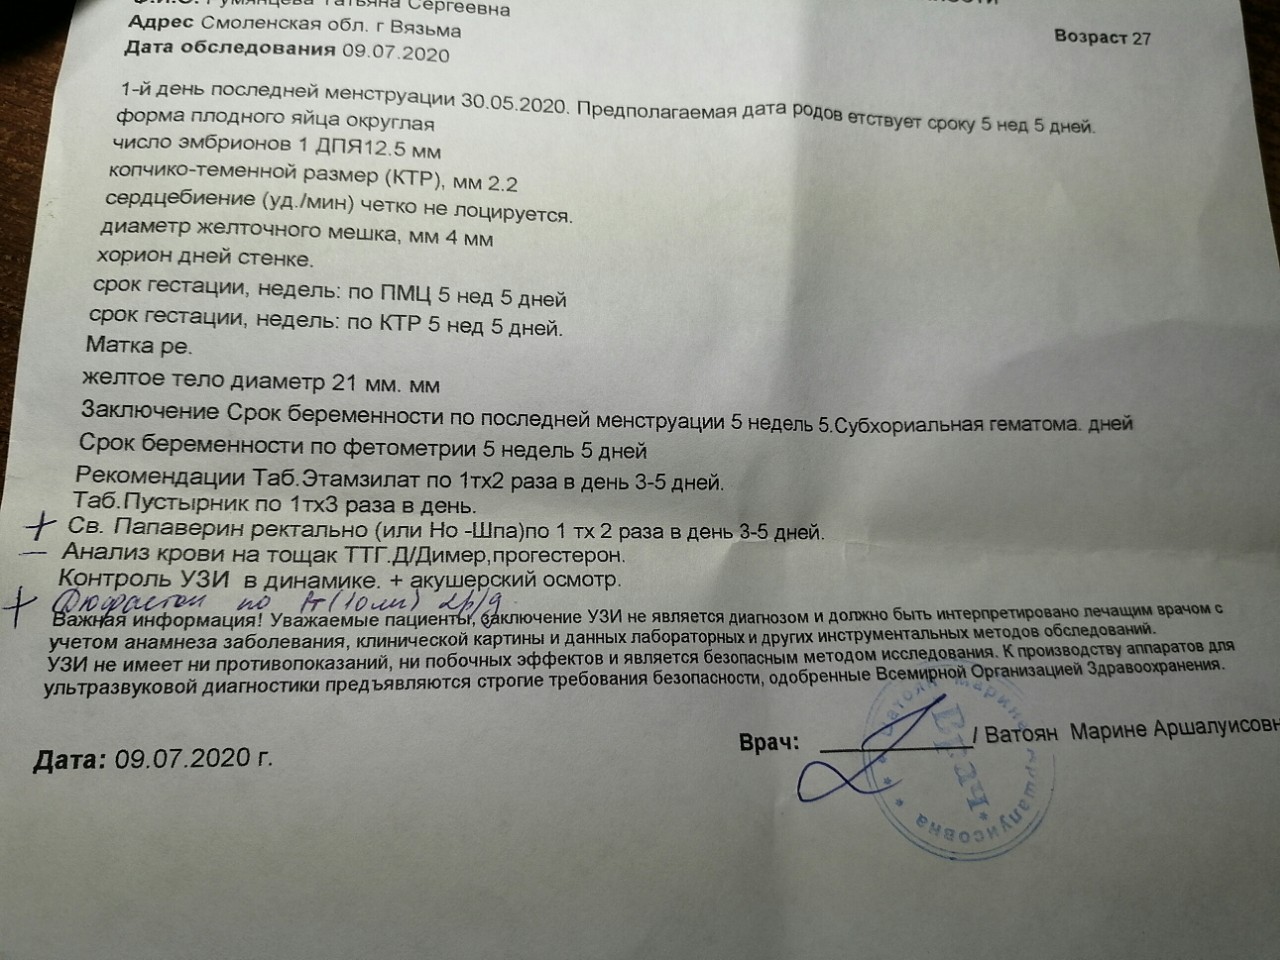

Фотографии на ранних этапах беременности

Раздел: Визуальный дайджест